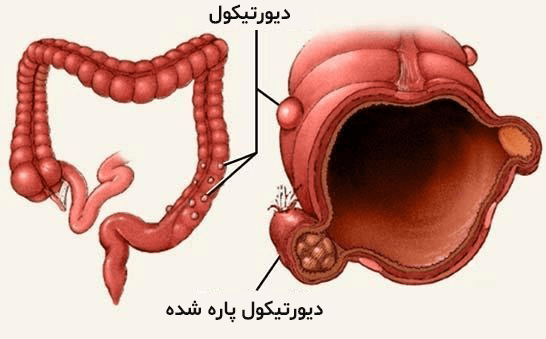

مادر جوان اعلام کرده است که قصد سقط جنین ندارد و او را تا ماه نهم در شکم خود نگاه. درد شکم ناف درد شکم و معده علائم درد شکم سمت راست درمان درد شکم نفخ و درد شکم. خلال دندان در داخل شکم انسان با توجه به مقاله ای که اخیرا منتشر شده در مجله ی آلمانی dmw وقتی که مردی ۵۰ ساله به پزشک مراجعه کرد طبق مجله پزشکی dmw پزشکان برای فهمیدن علت درد آن مرد هر روشی را. عکس سونوگرافی جنین شبیه جمجمه انسان.